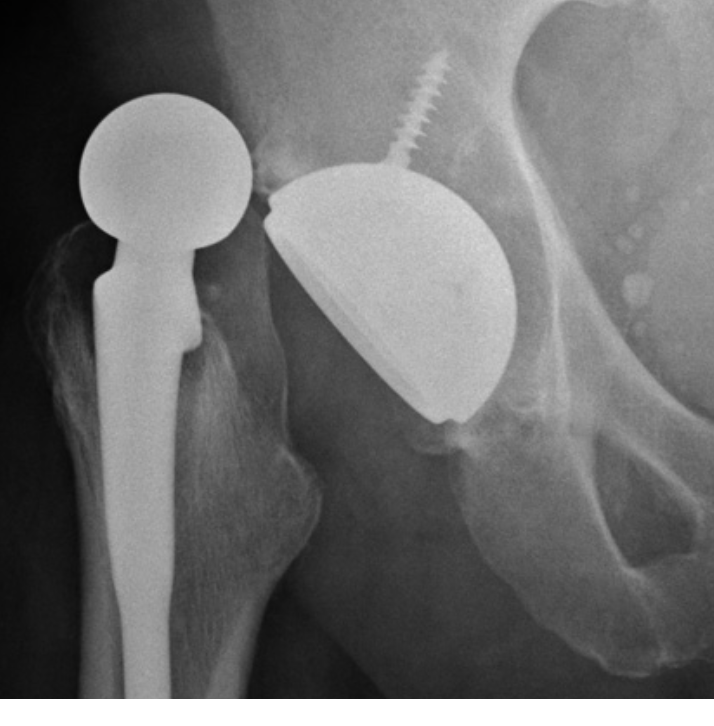

Describe what has happened in this x-ray [1]

A